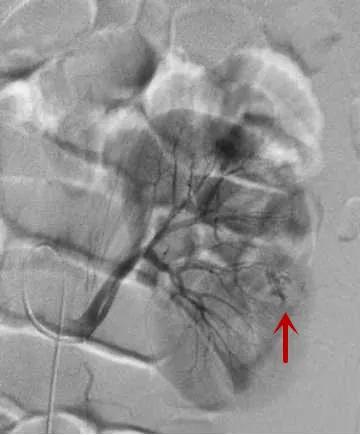

△造影找到出血动脉/找到出血责任动脉/精准栓塞后出血动脉已闭塞

△找到出血动脉/进行栓塞止血/再次造影明确出血已止住